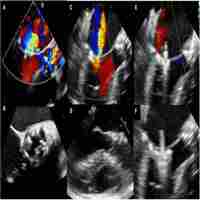

| Abstract | A 41-year-old woman was admitted to the hospital with a one-week history of increasing fatigue, weakness, and breathlessness. She had a persistent cough, haemoptysis, and a sharp pleuritic chest pain on the right the evening before admission. Her temperature was 36-3'C (oral), the respiratory rate was 30/min, the pulse was 130/min with atrial fibrillation, and the blood pressure was 110/66 mmHg. Examination did not reveal conjunctival petechiae, mucous membrane lesions, ulcerations, splinter haemorrhages, or Janeway lesions. Murmurs consistent with mitral stenosis, mitral regurgitation, aortic stenosis, and aortic regurgitation were present. There wras no calf tenderness, Homans' sign was absent, and neurological examination was within normal limits. The total leucocyte count was 15 800/mm' (neutrophils 70% and the SGOT and LDH were both raised. Chest radiograph demonstrated generalised cardiomegaly, prominent vasculature to the upper |